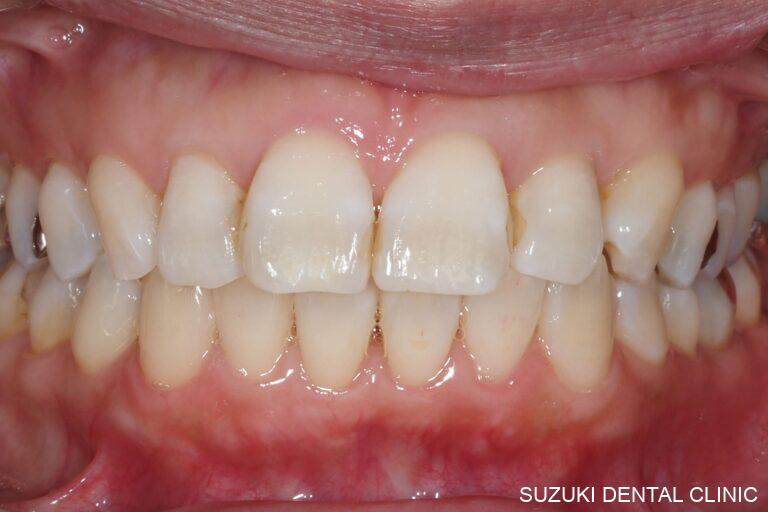

これまでの臨床経験による技術と、咬合理論を駆使して、機能と審美性を兼ね備えた美しい口元と快適な食生活を取り戻すことは、患者のQOLを高めると共に我々の存在意義を同時に揺るぎないものとすることと確信しています。